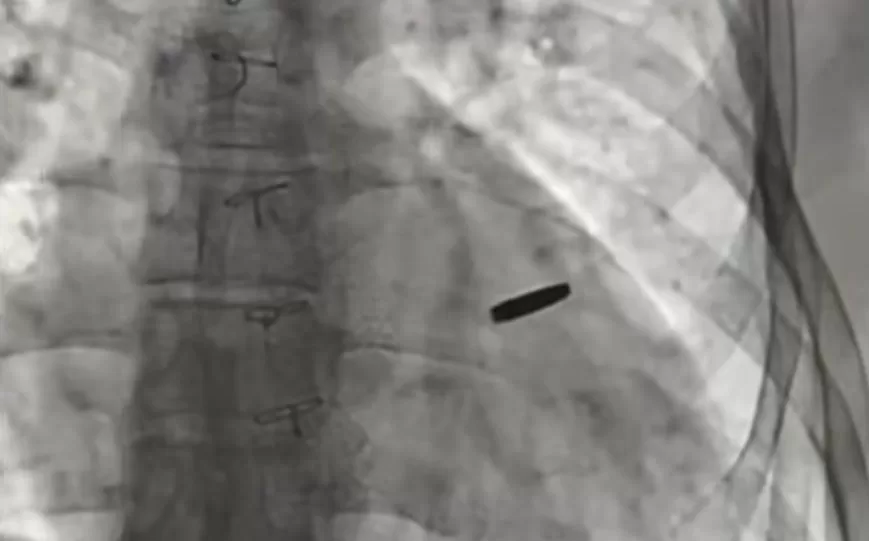

Куля в серці військового / Кадр з відео

З серця звільненого українського військового, який три роки перебував у російському полоні, видалили кулю.

Військовий захищав “Азовсталь” і був захоплений у полон під час оборони Маріуполя. Два місяці тому його обміняли, а під час медичного обстеження лікарі виявили кулю в серці.

“Три роки він жив із цією кулею. На щастя, вона не спричинила шкоди, і зараз ми її видалили. Хлопцю пощастило”, — зазначив Тодуров.